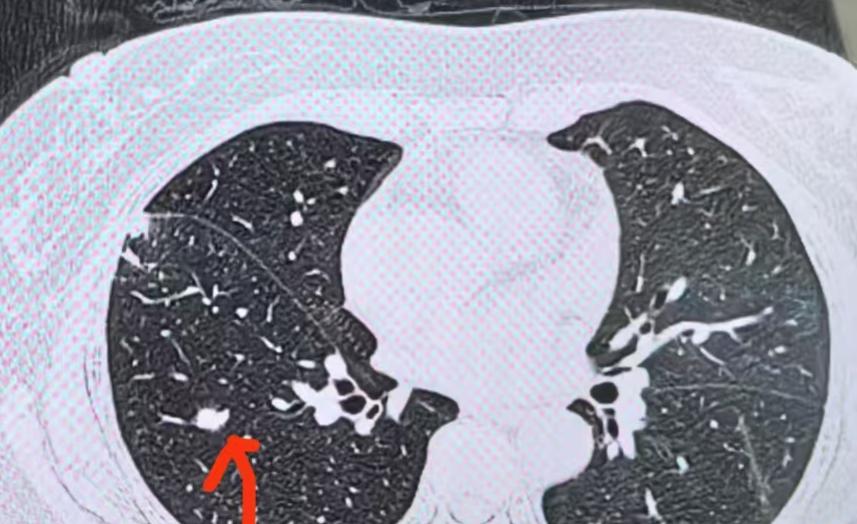

46岁女高管被诊断为肝癌,化疗2次后转院复查,被告知没有癌症 46岁这个年纪,正是很多职场人拼劲最足的时候,身体上的一点小毛病,很多人压根不当回事。这位女高管就是在一次单位组织的体检中查出肝部占位,进一步检查后被告知是肝癌,连犹豫都没来得及,就开始接受化疗。 但治疗进行到第二次时身体反应太大,于是转院复查,没想到结果直接反转:根本不是癌症,是良性的局灶性结节性增生。这一下连医生都皱起了眉头,原本“确诊”的癌症,竟然不是癌。 这种误诊在临床上不是孤例,特别是对肝部占位的判断,一旦影像不够清晰,或者肿瘤标志物轻度升高,就容易被直接归类为恶性。 问题是,有些良性病变,比如肝血管瘤、局灶性结节性增生,甚至肝腺瘤,在影像学上与早期肝癌非常接近。 尤其在增强CT或磁共振上,有些病灶的表现差异并不明显,加上医生经验、患者基础病史等影响,容易出错。 女高管当初被“确诊”时,是在地方医院,影像报告提示高密度团块,AFP轻微升高,医生根据这些结合肝区不适症状直接定性为肝癌。 但AFP这种标志物并不专属于肝癌,女性在月经、怀孕甚至某些良性肝病中也可能升高。真正具有特异性意义的是动态观察和病理活检。 这名患者直到转院后才接受肝穿刺检查,最终证实是良性病变,无需化疗也无需手术,只需定期观察。 医生也提到,有些人得知自己得癌后会非常焦虑,情绪上的冲击会加速身体状态恶化。反而是那些误诊为癌症、最后查明不是的人,在心理上受到的打击和恢复期更长。 这位女高管就是在短短两个月内经历了情绪崩溃、盲目治疗、副作用袭来,结果等真相出来,整个人也被拖垮了一截。这种损耗,不是数据能看出来的,但对身体的影响很真实。 医学上把这类情况称作“假阳性”,它不意味着诊断技术低级,而是临床实践中存在误差范围。特别是在癌症筛查中,误诊和漏诊同样令人头疼。 医生强调,如果没有明确的组织病理学证据,不建议马上进入治疗流程。尤其是一些影像上可疑但无症状、标志物升高不明显的情况,更适合先动态观察、综合评估,而不是立刻启动化疗。 这事也给很多人敲响了一个提醒:查出肿块不能马上等于癌,做决定前得确认病理结果,不能光看影像和指标。 否则误伤身体不说,还会拖慢真正的健康恢复。很多癌症确诊的关键节点,不是查得早,而是查得准。现代医学再发达,也不能完全依赖机器输出,医生判断和患者沟通才是避免误诊的关键部分。 那位女高管经历的,是医学误差中的典型样本,也是健康决策里最容易忽略的一环。不是每个被说成癌症的影像结果都是真的,也不是每一个治疗开始都代表准确。 医学这事,急不得,更不能光靠直觉和经验。有时候,做对一次穿刺检查,比接受一轮错误化疗更重要。 身体不怕出问题,怕的是没弄清楚就先下了结论。误诊不是病,治错了才是伤。看明白了这一点,也许就少了一场不必要的折腾。